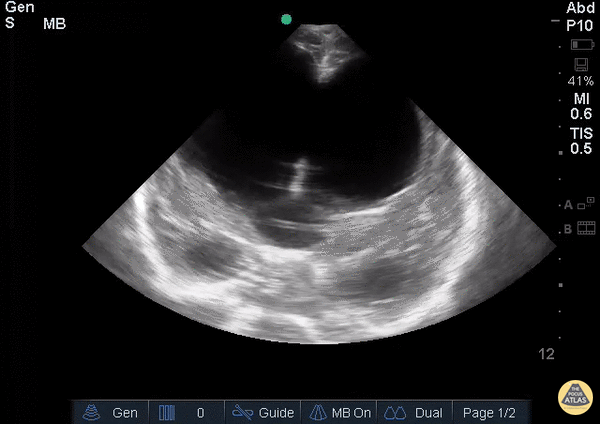

View: Unspecified Parasternal Long Axis Parasternal Short Axis Apical Four-Chamber Subcostal Four-Chamber Subcostal Inferior Vena Cava Right Upper Quadrant Left Upper Quadrant Suprapubic Longitudinal Suprapubic Transverse Subxiphoid Anterior Thoracic Phrenic